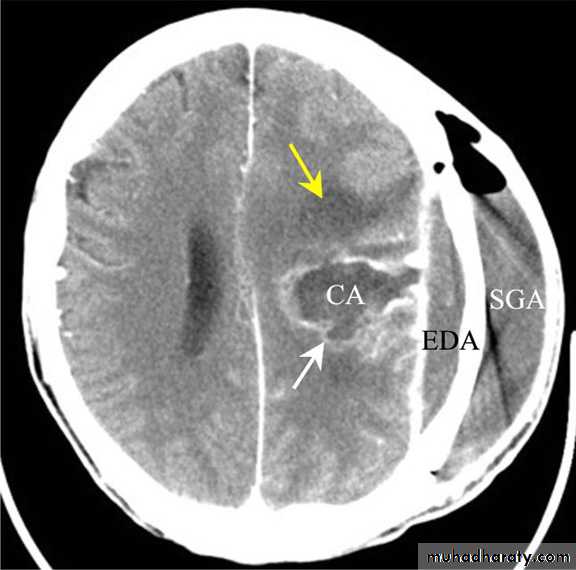

SUBDURALEMPYEMA

Subdural EmpyemasSource of infection:

Although uncommon, may develop following sinusitis or mastoiditis.

It carries a high mortality (5-10 %)Subdural Empyemas

• Clinical picture:Headache, fever and meningism.

Seizures are common.

Focal neurological deficits which may progress rapidly to:

Altered mental state and coma.

• NOTE: The combination of fever and seizures with background of sinusitis is usually diagnostic of this lesion.

Subdural Empyemas

Investigations:

CT scanning;

Despite subdural empyema is a neurosurgical emergency, diagnosis is often delayed as the collection on CT is usually so slight and frequently missed.Subdural Empyemas

• Treatment:Craniotomy and thorough drainage of the pus, followed by:

Intravenous antibiotic.

Anticonvulsants.